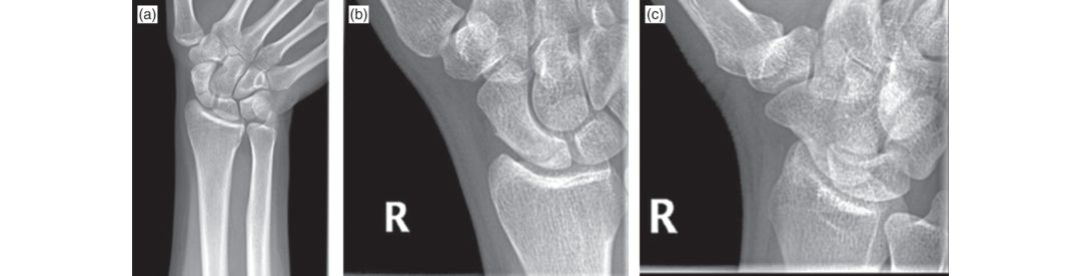

# تدبير كسور العظم الزورقي: دليل شامل ## مقدمة حول كسور العظم الزورقي تعتبر كسور العظم الزورقي من الإصابات الشائعة ال…